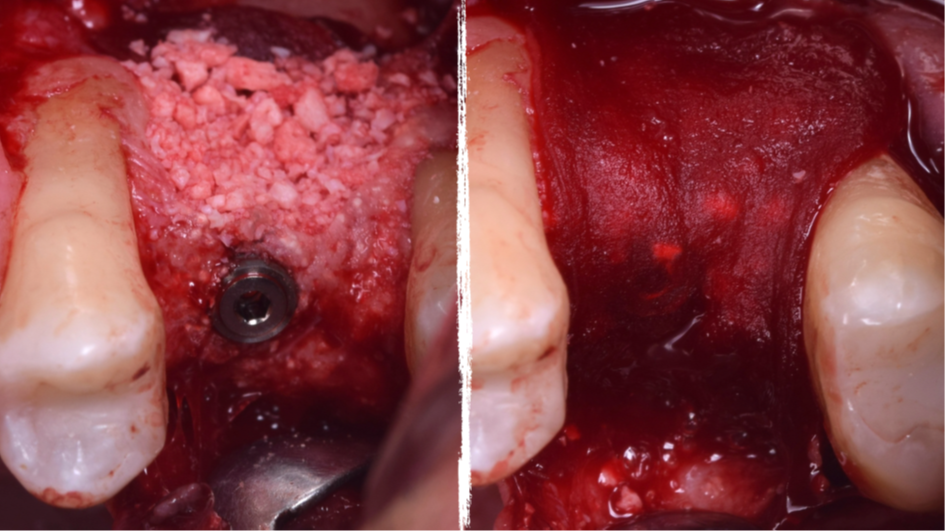

A técnica da janela lateral desenvolvida por Cadwell-Luc e modificada por Tatun na década de 1970, ainda é uma técnica previsível de sucesso para levantamentos de assoalho de seio maxilar e enxertos ósseos, pois apresenta a segurança de visualização da membrana de Schneider no processo de levantamento, quando comparada a outras técnicas de abordagem crestal.

Uma vez realizada a técnica de levantamento de seio maxilar e insucesso no ganho ósseo, a reintervenção torna-se mais complexa devido a remoção da parede vestibular e colabamento da membrana de Schneider com a mucosa vestibular.

O presente trabalho tem como objetivo fazer um relato de caso clínico de reintervenção em enxerto ósseo para levantamento de seio maxilar pela técnica da janela lateral com instalação simultânea de implante Maestro Superiore.